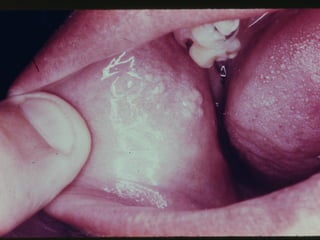

Leucoedema

• Etiologia

• Características Clínicas

• Raça

• Manobra Clínica

• Aspectos Histológicos